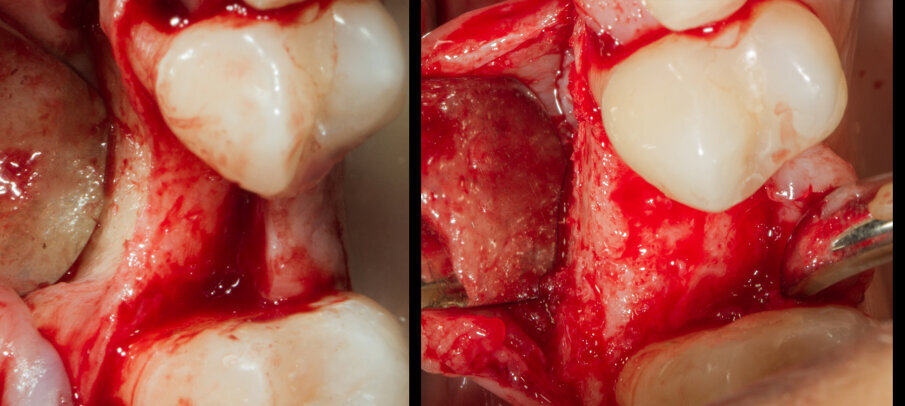

Si programma un intervento di GBR con rigenerazione ossea orizzontale mediante utilizzo di granuli di sostituto osseo eterologo (OsteoBiol Gen-Os) e un device riassorbibile costituito da osso corticale eterologo (OsteoBiol Lamina Soft). A 10 mesi verrà inserito un impianto differito. Dopo aver inciso un lembo mucoperiosteo con incisioni di scarico verticali e scollato sino alla parte più apicale del vestibolo si apprezza l’estrema sottigliezza della cresta residua e la sua corticalizzazione (Figg. 5, 6). Vengono praticati dei fori di 1,4 mm di diametro nella corticale vestibolare per esporre la midollare interna e aumentare la vascolarizzazione del particolato osseo che verrà innestato nel difetto osseo (Fig. 7).

Fig. 5 - Il marcato avvallamento osseo è presente in tutta l’altezza del vestibolo.

Fig. 6 - Visione crestale del difetto osseo.

Fig. 7 - Visione vestibolare del difetto osseo.